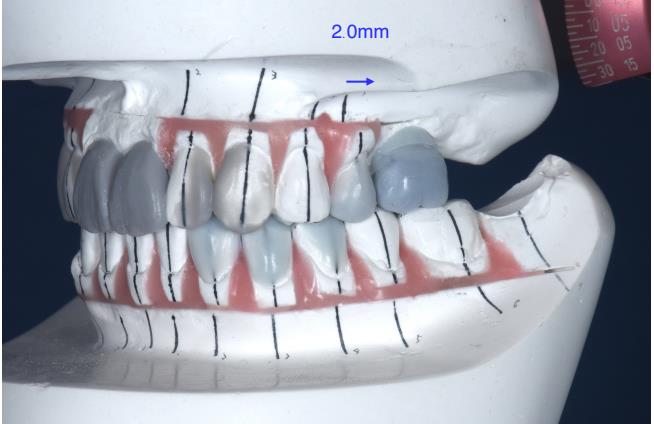

歯並びを理想的にデザインしたセットアップモデルを見ると、全体的な歯の移動量は2ミリ程度で小さく、本ケースではまず左上にインプラントを入れてから矯正を行いました。(図3)